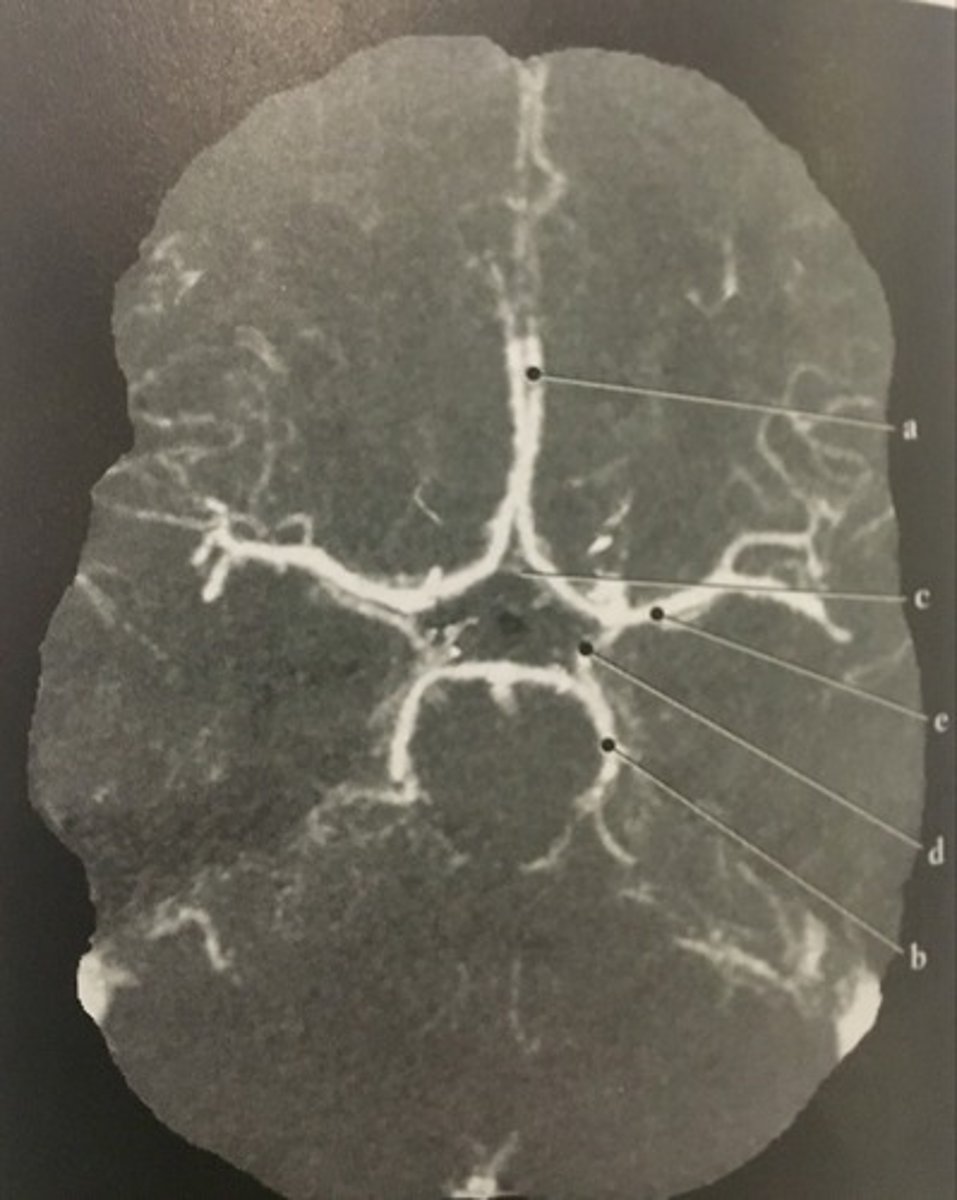

Vein of Galen

Identify structure B on this axial CT slice of the brain.

<p>Identify structure B on this axial CT slice of the brain.</p>

Internal cerebral veins

Identify structure C on this axial CT slice of the brain.

<p>Identify structure C on this axial CT slice of the brain.</p>

Thalamostriate vein

Identify structure D on this axial CT slice of the brain.

<p>Identify structure D on this axial CT slice of the brain.</p>

Straight sinus

Identify structure E on this axial CT slice of the brain.

<p>Identify structure E on this axial CT slice of the brain.</p>

Anterior cerebral artery

Identify structure A on this axial CTA of the Circle of Willis.

<p>Identify structure A on this axial CTA of the Circle of Willis.</p>

Posterior cerebral artery

Identify structure B on this axial CTA of the Circle of Willis.

<p>Identify structure B on this axial CTA of the Circle of Willis.</p>

Anterior communicating artery

Identify structure C on this axial CTA of the Circle of Willis.

<p>Identify structure C on this axial CTA of the Circle of Willis.</p>

Posterior communicating artery

Identify structure D on this axial CTA of the Circle of Willis.

<p>Identify structure D on this axial CTA of the Circle of Willis.</p>

Middle cerebral artery

Identify structure E on this axial CTA of the Circle of Willis.

<p>Identify structure E on this axial CTA of the Circle of Willis.</p>